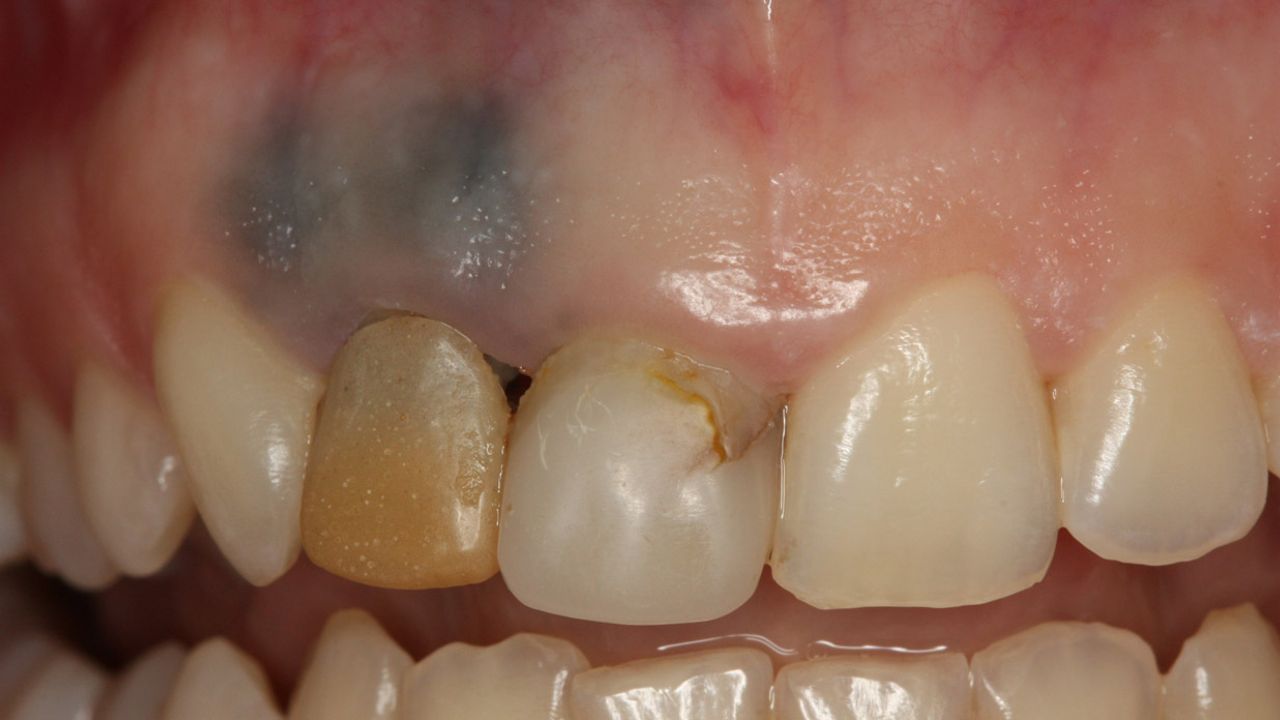

Diş eti melanomu, ağız boşluğundaki pigment üreten hücrelerden kaynaklanan ve genellikle üst çene diş etinde ortaya çıkan bir tümör. Siyah, kahverengi, mavi veya kırmızı renkte görülebilen bu lezyonlar, başlangıçta ağrı yapmayabilir ve bu nedenle fark edilmeyebilir.

Bu kanser türü nadir görülse de tüm ağız kanserleri içinde önemli bir yer tutuyor. En tehlikeli yanı, erken dönemde hızla çevre dokulara yayılabilmesi ve kısa sürede metastaz yapabilmesi. Bu yüzden uzmanlar, her pigmentli lekenin ciddiyetle değerlendirilmesi gerektiğini söylüyor.